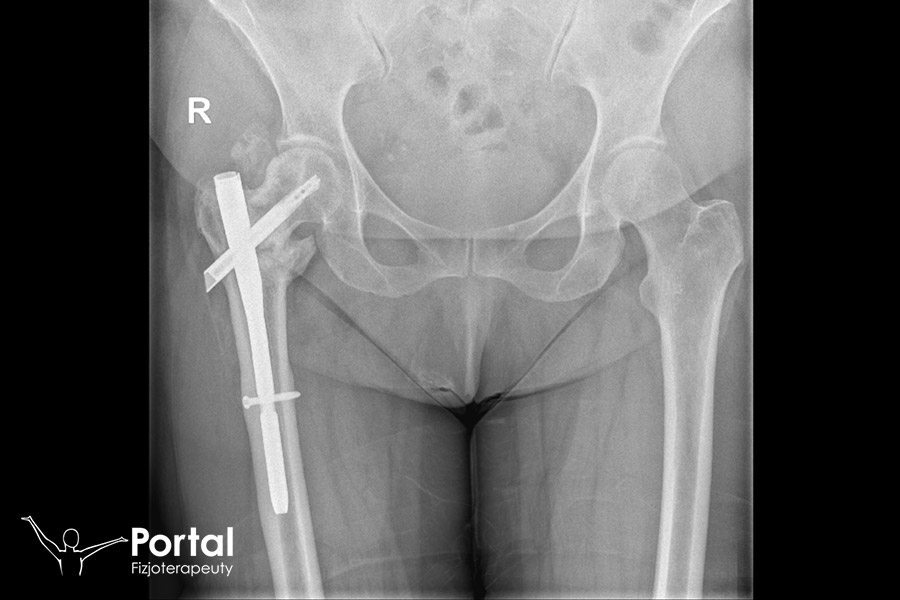

Gwóźdź śródszpikowy

Gwóźdź śródszpikowy to sterylny przedmiot wykorzystywany w chirurgii ortopedycznej do wewnątrzustrojowej stabilizacji odłamów, które powstały wskutek złamania kości. Jest wykonany